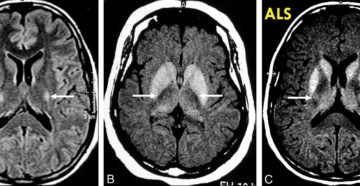

Боковой амиотрофический склероз — что это, причины, симптомы Боковой амиотрофический склероз — это дегенеративное заболевание…